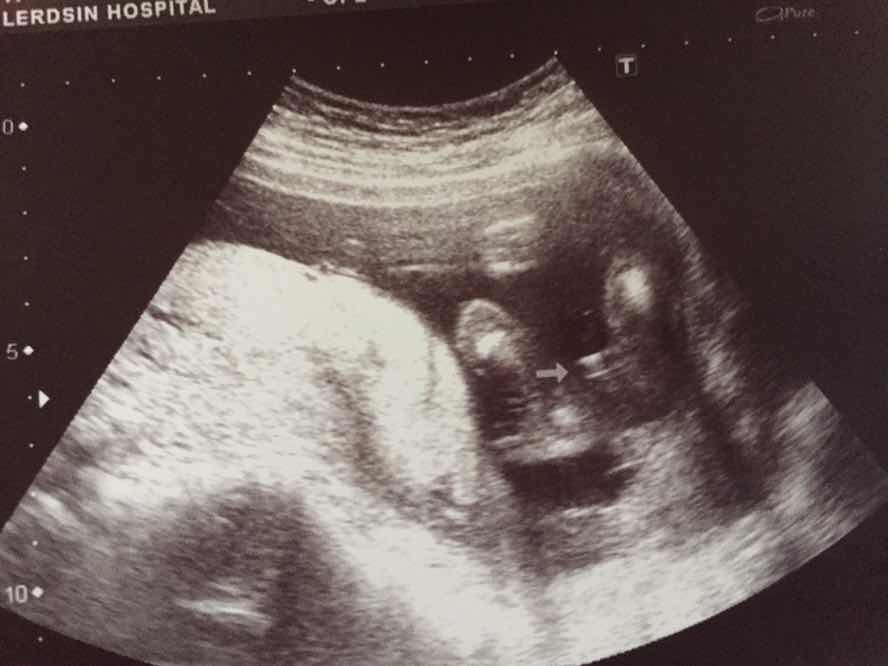

แฝดชายหญิง28ก.ค.คะ

30 ก.ค. ได้ผู้ชายคะ

5 ก.ค ผู้กญิงจร้าา

ผู้ชายค่า😊

หมอบอกผู้ชายค่ะ

4 ก.ค ผู้หญิงค่ะ😄

15 ก.ค ชายค่ะ

ตอน17+5ค่ะตอนนี้21+1

ผช..จร้า7ก.ค.

ผู้หญิงค่ะแม่😘